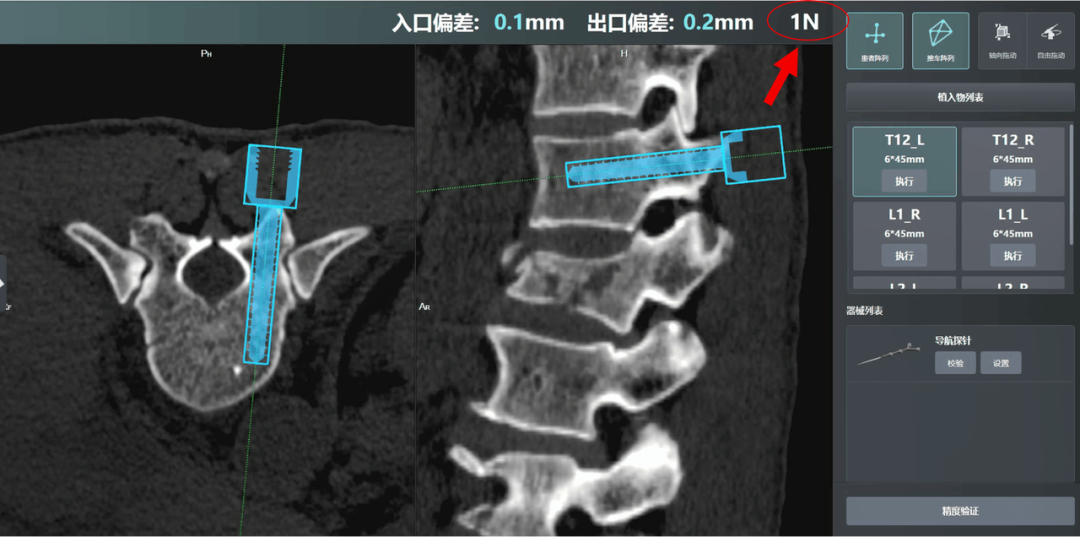

常规机器人辅助脊柱手术时,置针/钉时术中缺乏即刻反馈,不能对置针/钉精准性进行实时判断与调整,提升了手术操作门槛。

联影智融脊柱创伤一体化骨科手术机器人依托六维力传感器核心技术,创新性提出末端力反馈实时监测系统,将原本“凭经验判断”的操作转化为“量化数据支撑”的科学决策。该系统通过实时采集机械臂末端力感数据,量化分析影响定位精度的临床因素,为医生提供精准误差修正依据,将传统“经验判断”转化为“数据支撑”,有效提升手术精准度,推动骨科手术标准化发展。

末端精准力学显示